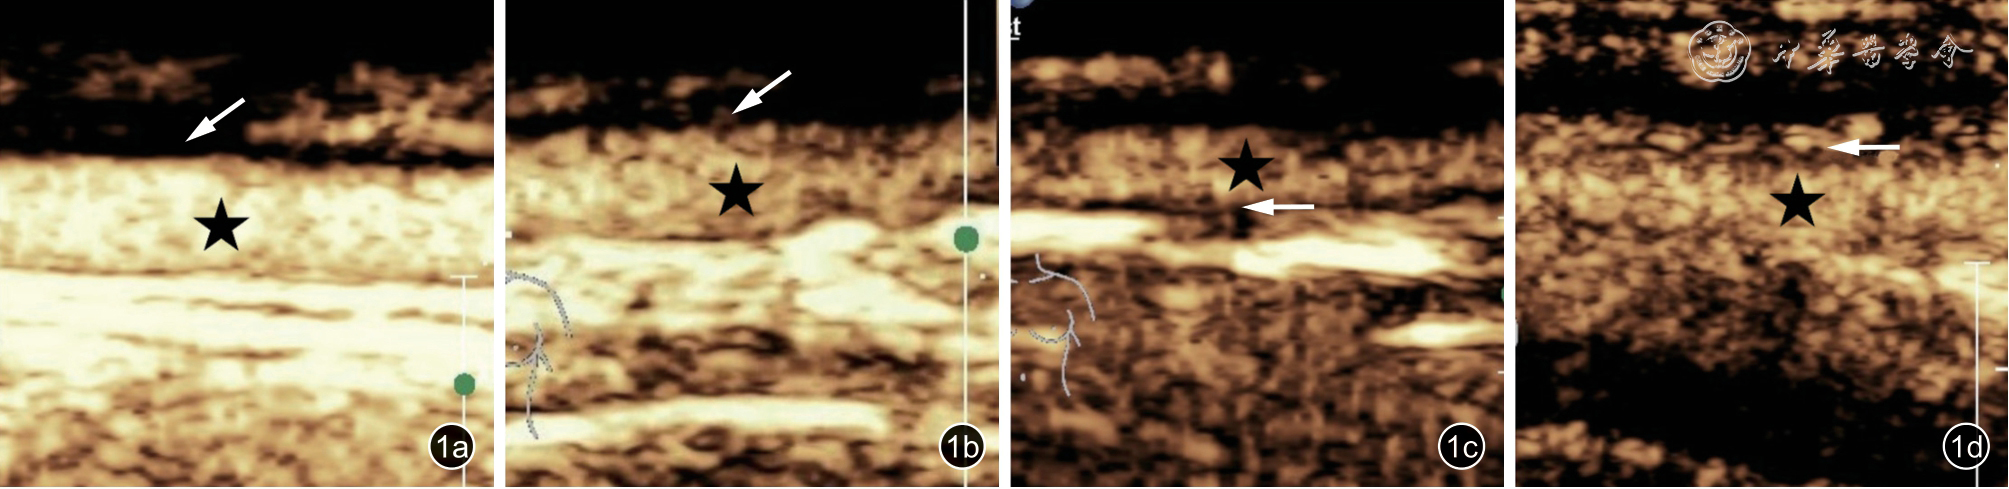

2.仪器与检查方法:采用Philips EPIQ7 仪器进行超声检查,eL18-4 线阵探头。嘱患者平卧位,头偏向一侧,被检查部位涂抹足量耦合剂或使用导声垫,先行常规超声检查,采用二维超声及彩色多普勒超声观察并评估颞浅动脉管径和内中膜有无增厚,局部放大后在横切面上测量IMT 较厚处的管径和IMT。管径是从颞浅动脉一侧的外膜到对侧外膜之间的垂直距离,IMT 为血管后壁内膜上缘与外膜上缘之间的垂直距离。当IMT>0.3 mm时,认为IMT 增厚11,12。CEUS 时采用低机械指数(机械指数=0.06),探头轻轻置于颞浅动脉上方,选取双侧颞浅动脉较厚IMT 处的纵切面为观察目标,局部放大以清晰显示颞浅动脉的管壁结构为佳。将SonoVue 1.2 ml 通过肘正中静脉以弹丸式注射,随后用5.0 ml 生理盐水冲管,记录CEUS图像,连续观察2 min。根据颞浅动脉管壁增强情况,将CEUS 结果统一分为4 级13:0 级,无增强;1 级,少许点状增强;2 级,较密集点状增强;3 级,弥漫性点、线状增强(图1)。参照既往TA的CEUS 研究14,15,以CEUS 分级≥2 级作为评价颞浅动脉GCA 患者活动期的标准。所有CEUS分级均由2 名具有5 年以上CEUS 工作经验的医师分别完成,当2 名医师分级结果不统一时则通过讨论决定最终分级;如讨论后意见不统一,则由第3 名高年资超声医师决定最终分级结果。

图1 颞浅动脉巨细胞动脉炎患者的不同超声造影表现。图a 显示管壁内未见明显造影剂灌注,评级为0 级;图b 为管壁内造影剂呈少许点状灌注,评级为1 级;图c 显示管壁内较密集点状灌注,评级为2 级;图d 显示管壁内造影剂呈弥漫性点、线状灌注,评级为3 级(★示管腔,白色箭头示颞浅动脉增厚的内中膜)